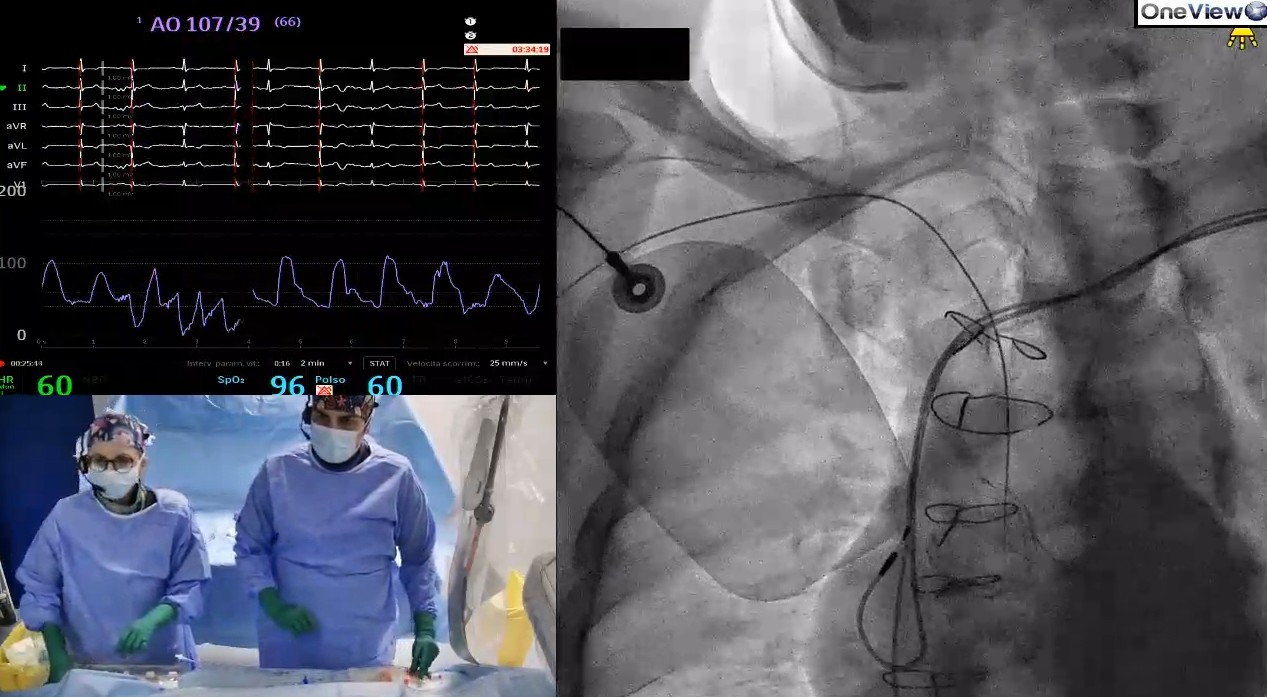

Ulteriore innovazione è stata l’utilizzo durante l’intervento del sistema OneView, tecnologia che consente di registrare l’intera procedura e trasmetterla in diretta, permettendo così ad altro personale medico collegato da altri centri di assistere all’intervento in tempo reale, rendendo possibile uno scambio di informazioni e una collaborazione a distanza durante le procedure, oltre ad una formazione continua del personale.

Il sistema OneView è progettato per rivoluzionare l’educazione digitale non solo per la cardiologia interventistica, ma anche nell’ambito della radiologia e della chirurgia vascolare. Questo sistema consente di acquisire fino a otto dispositivi digitali (tra cui fluoroscopio, ultrasonografia intravascolare, tomografia a coerenza ottica, poligrafo, ecografo etc.) ed è costituito da: postazione di lavoro, due telecamere di sala, auricolari per il personale medico.